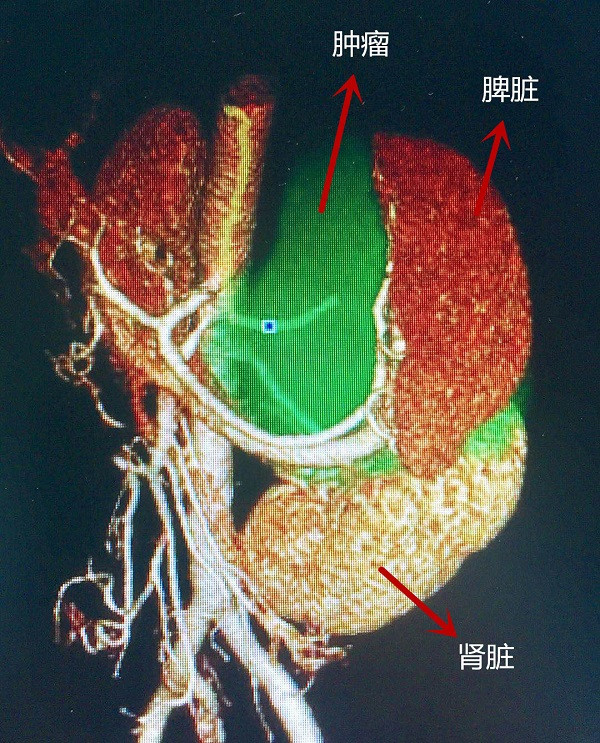

“手術(shù)切除嗜鉻細(xì)胞瘤是最有效的治療方法,但像潘女士這樣的情況,腫瘤與腹主動脈等多臟器血管粘連,手術(shù)風(fēng)險極高?!标悩I(yè)輝介紹,為了提高準(zhǔn)確性,術(shù)前,影像科的醫(yī)生通過“臟器重建”,將重要的部位突出顯示,精準(zhǔn)定位腫瘤的位置、血液供應(yīng)情況及腫瘤與周圍臟器的關(guān)系。

“從‘臟器重建’的圖中,我們可以清晰地看到腫瘤、脾臟、腎臟的關(guān)系,巨大的腎上腺腫瘤,明顯壓迫到了脾臟和左側(cè)腎臟?!?陳業(yè)輝說。